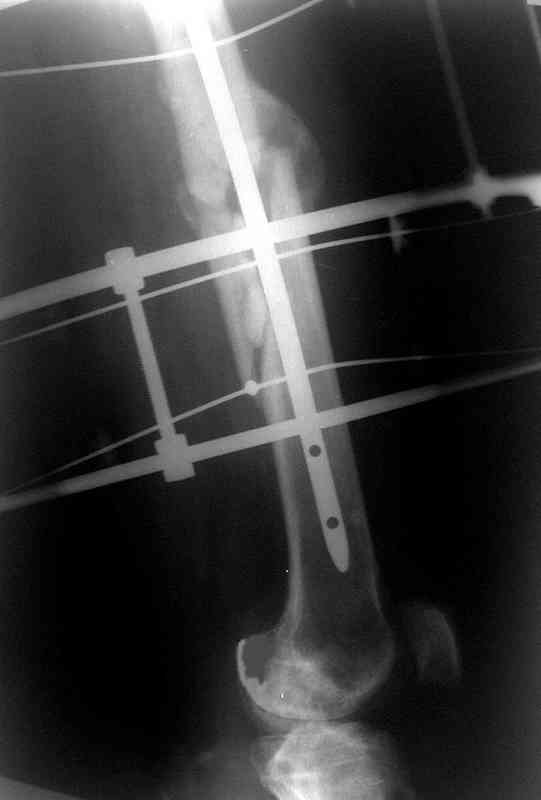

Уважаемые коллеги!На прилагаемых снимках - состояние после оперативного вмешательства (открытый перелом левого бедра в средней трети):

МОС, стержень нефиксированный. С момента операции прошло 8 месКак по Вашему мнению происходит консолидация? Допустимо ли смещение или необходима повторная операция по выравниванию конечности? Если да, какой метод рекомендуете (фиксированный стержень, пластина)?Буду благодарен за оперативный ответ.

Вы не пишете, есть ли сейчас болезненные проявления, и какие. Как пациент ходит. Какова функция колена. Ось выглядит приемлемо. Рентгенологически на сращение непохоже. Если есть клиника несращения (боль, хромота), то лучший выбор - закрыто рассверлить и перештифтовать блокированным гвоздем. Желательно определиться поточнее, нет ли проблемы с длиной , чтобы попутно и ее решить. И не создать. Ну и прежде всего исключить инфекцию. Если это инфицицированное несращение, план надо другой.

При таком диаметре штифта не удивительно, что перелом не сросся (кстати, какой диаметр и что за модификация штифта?).

Как по Вашему мнению происходит консолидация?

По-моему - замедлнно.

Допустимо ли смещение...

В этой проекции угловое смещение градусов 15-20 - многовато будет. Есть ли укорочение?

...или необходима повторная операция по выравниванию конечности? Если да, какой метод рекомендуете (фиксированный стержень, пластина)?

Удалить, исправить ось, рассверлить, заштифтовать блокируемым гвоздем.